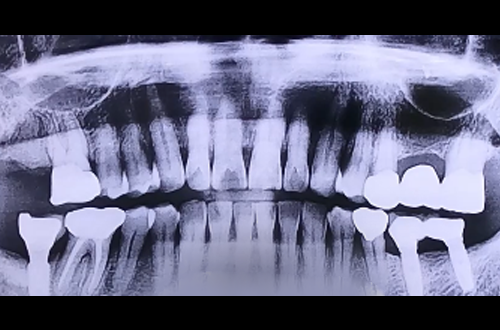

BEFORE

한 달 전 다른 치과에서 오른쪽 가장 큰 어금니를 뺀 주변의 뼈들이 다 녹고 잇몸이 많이 약해져 있었던 환자분이십니다.

잇몸뼈가 많이 약해져 있어 뼈 이식을 하신 뼈들이 단단하게 굳으면 이후 임플란트를 진행하는 것으로 계획을 잡고 진행하였습니다.